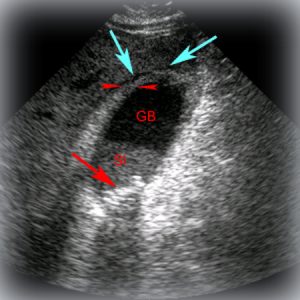

Ecografia evidenţiază prezenţa calculilor.